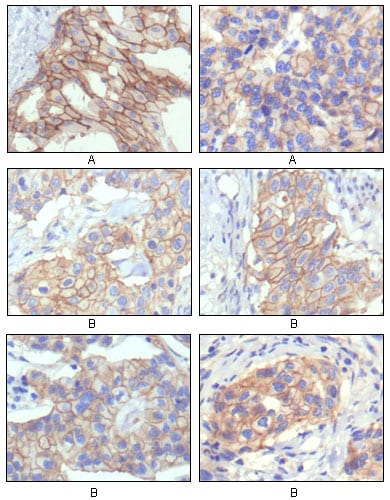

- Immunohistochemical analysis of paraffin-embedded human prostate tissues using GSTP1 mouse mAb with DAB staining.